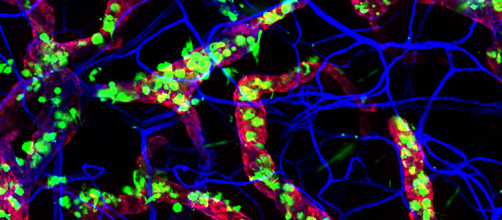

Des immunothérapies efficaces contre les cancers colorectaux